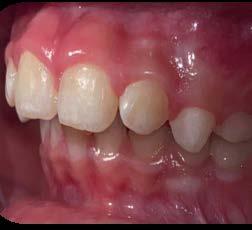

Sobremordida vertical excesiva en paciente pediátrico. Caso clínico

Estudio comparativo de la precisión entre 2 distintas técnicas

Las restauraciones indirectas son el día a día de la odontología, por lo tanto es de suma importancia conocer los diferentes sistemas para tomar impresiones dentales, ya sea convencionales o modelos digitales. Objetivo: comparar la precisión de la toma de impresión convencional con polivinil siloxano (Elite P&P) vs. el uso de una técnica de escanéo digital. Metodología: estudio transversal, comparativo, observacional e in vitro. En un tipodonto Nissin se realizó una serie de señalizaciones las cuales se fijan con cianocrilato para posteriormente tomar una impresión convencional, se fijan los vástagos con patern resin en la impresión y se vacía con yeso tipo IV de Zhermack, después se realizó un escaneo digital al tipodonto para así comparar

las distancias entre los diversos puntos marcados, esto con un vernier eléctrico. Resultados: se obtuvieron resultados ligeramente significativos entre las 2 distintas formas de obtener un modelo de trabajo. Conclusión: Según los hallazgos encontrados en este estudio, se determinaron las siguientes conclusiones: es de suma importancia utilizar los materiales como lo marca el fabricante. Los resultados obtenidos requieren estudios más precisos, pero pudimos determinar que los tiempos de trabajo son menores con la técnica digital, y por ende requiere menor ajuste.